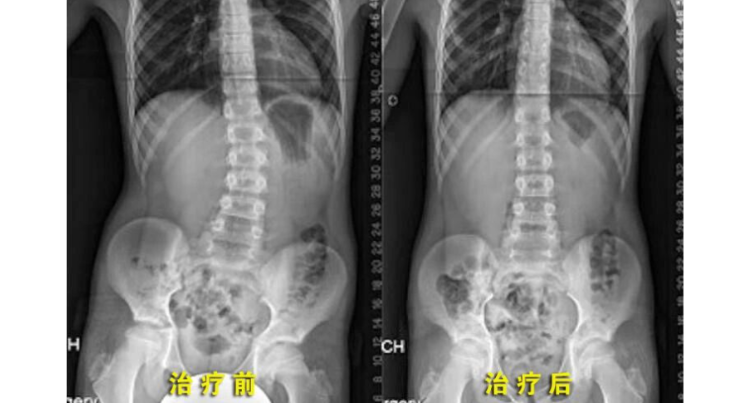

孩子脊柱侧弯,居然是因为“长短腿”?